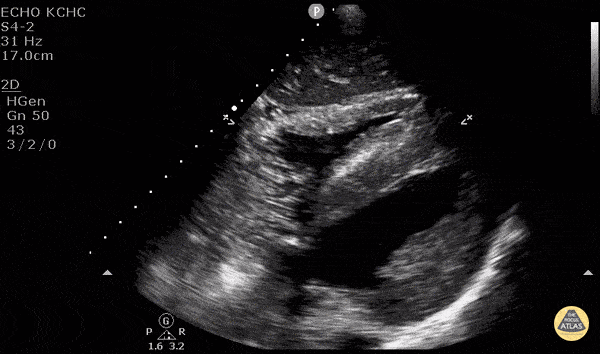

Normal Cardiac Anatomy - Central Line Confirmation

After placing a central line, POCUS can be used to rapidly and accurately assess correct venous placement as well as exclusion of pneumothorax prior to confirmation via a CXR. Simply attach an agitated flush to the central line, get a good view of the right side of the heart (here we used the subxiphoid view) then flush rapidly. If you see bubbles pass from the right atrium to the right ventricle of the heart, you know you’re good to go. POCUS has a sensitivity of 86.8% and specificity of 100% for identifying correct central venous catheter placement. See our evidence atlas for more information. PMID: 28123616 If you placed this under direct visualization you know you aren’t likely to have caused a pneumothorax… but POCUS can rule that out too! (Look for lung sliding, lung point, B lines, and lung pulse.) Devki Joshi MS4 - SUNY Downstate Medical School, Dr. Matthew Riscinti and Dr. Isaac Gordon - Kings County Emergency Medicine